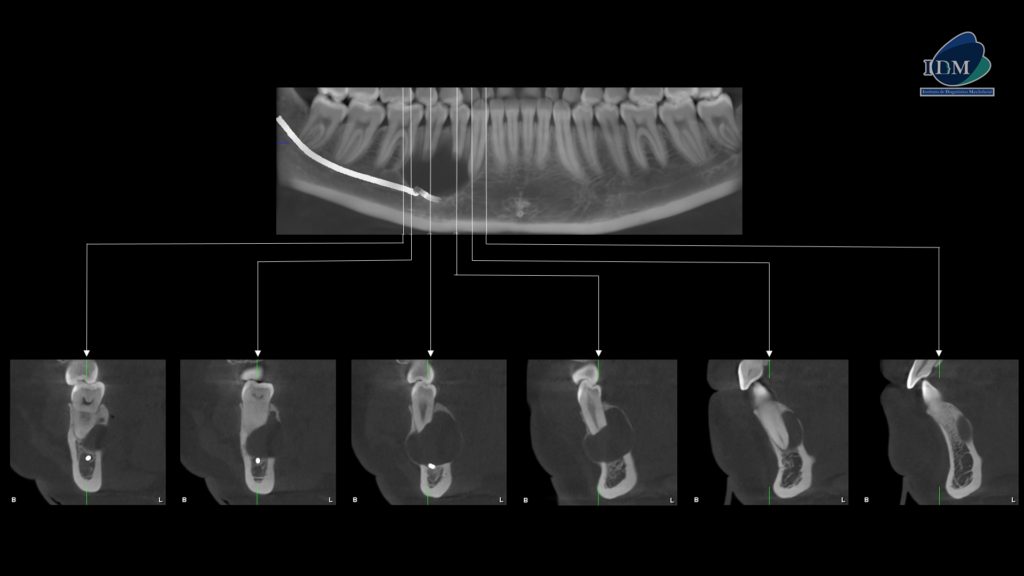

A la evaluación de la tomografía volumétrica (CBCT) en los cortes axiales (Figura 2) y transaxiales (Figura 3), se aprecia imagen isodensa unilocular que se extiende en sentido cefálico caudal desde cima del reborde alveolar hasta la cortical superior del conducto dentario inferior, en sentido mesio distal desde mesial de pieza 16 hasta

apical de pieza 13, que ocasiona borramiento parcial de la lámina dura de piezas 16, 15, 14 y 13, reabsorción radicular del tercio apical de pieza 14 y 15, borramiento parcial de la cortical superior del conducto dentario inferior y agujero mentoniano, adelgazamiento y expansión de tabla ósea vestibular; adelgazamiento, expansión y erosión de tabla ósea lingual. En las reconstrucciones 3D se representa de manera didáctica el compromiso que tiene la lesión con las estructuras adyacentes. (Figura 4).

RECONSTRUCCIÓN 3D